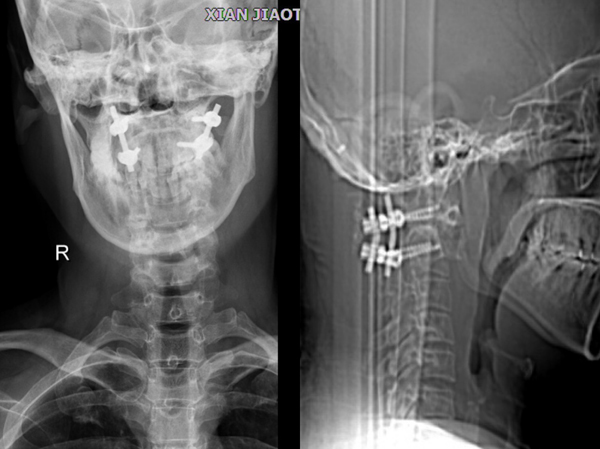

术前X线

术后X线